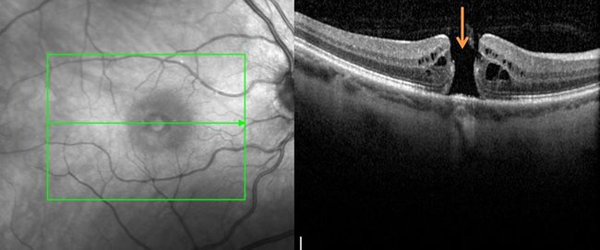

Le trou maculaire est une ouverture au centre de la rétine entraînant une diminution marquée de l’acuité visuelle.

La chirurgie est similaire à celle des membranes épimaculaires :

• vitrectomie,

• pelage de la membrane,

• injection de gaz expansif aidant à refermer le trou.

La présence de ce gaz interdit également les vols en avion pendant trois semaines.